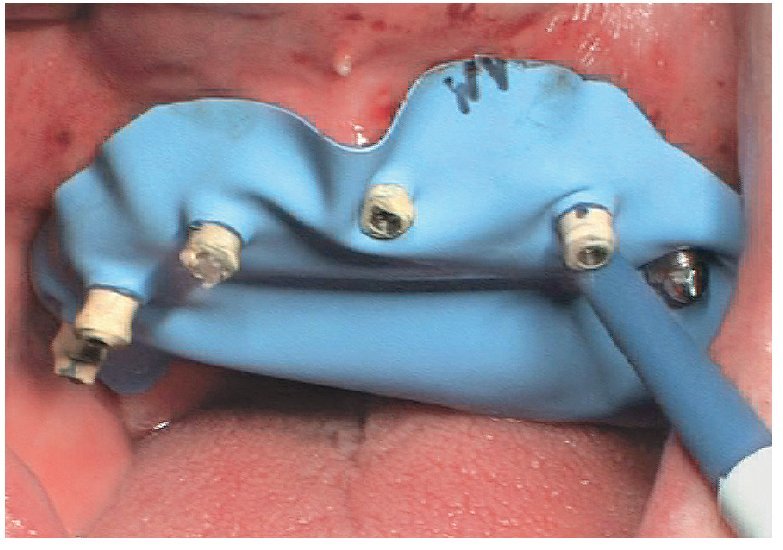

Fig. 66. Los pilares provisionales se aíslan de la cavidad oral mediante dique de goma antes de unirlos a la prótesis provisional.

Fig. 67. Se une la prótesis provisional a los pilares provisionales.